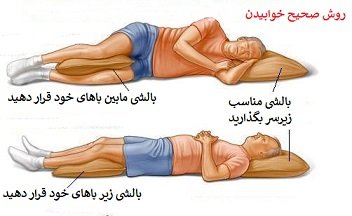

در کشیدگی گردن یک گردنبند طبی نرم دور گردن ببندید . داروهای مسکن ضد التهابی مانند آسپرین یا بروفن درد را کم میکنند . استفاده از بالشت مناسب موجب کاهش فشار به گردن میشود. پزشک ممکن است از داروهای شل کننده عضلانی برای کاهش اسپاسم عضلات استفاده کند . گاهی اوقات از روش های دیگری مثل ماساژ، اولتراسوند و تراکشن هم برای کمک به درمان استفاده میشود. اغلب کشیدگی های گردن در عرض 6-4 هفته خوب میشوند . البته کشیدگی های شدیدتر ممکن است برای بهبودی کامل به زمانی بیش ار این نیاز داشته باشند